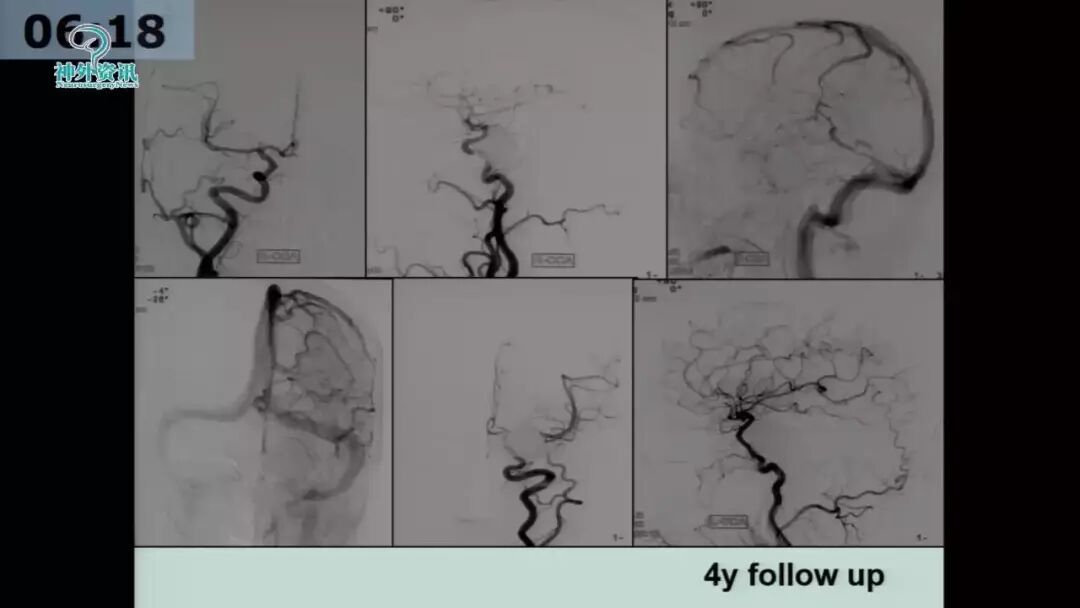

许奕教授:海绵窦区脑膜动静脉瘘的介入治疗